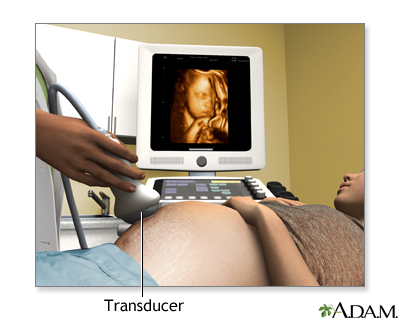

An ultrasound machine makes images so that organs inside the body can be examined. The machine sends out high-frequency sound waves, which reflect off body structures. A computer receives the waves and uses them to create a picture. Unlike with an x-ray or CT scan, this test does not use ionizing radiation.

The test is done in the ultrasound or radiology department.

- A handheld probe called a transducer is moved over the area being examined. You may need to change position so that other areas can be examined.

- Pregnancy